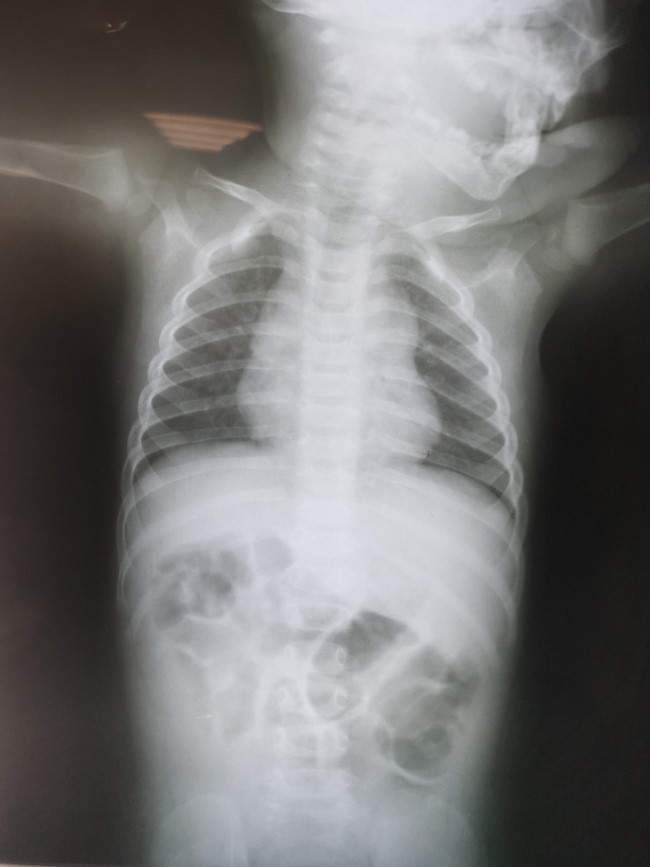

- Рентген органов брюшной полости. Помогает визуализировать воздушные кисты, определить размер и положение.

- Ирригоскопия. Введение контраста под рентген улучшает визуализацию и позволяет не только подтвердить диагноз, но и выявить некоторые причины развития пневматоза.

При ограниченном пневматозе кишечника из-за отсутствия выраженных специфических симптомов диагностика достаточно затруднена. Но иногда при глубокой пальпации желудка можно прощупать небольшие округлые образования по ходу кишечного тракта, которые напоминают виноград. Для точной диагностики проводят следующие исследования:

- обзорная рентгенограмма брюшной полости. Он определяет пузырьки газа разного размера, расположенные в цепочку. Пневматизированная кишка характеризуется наличием двойных кольцевидных теней в области вздутых петель кишки;